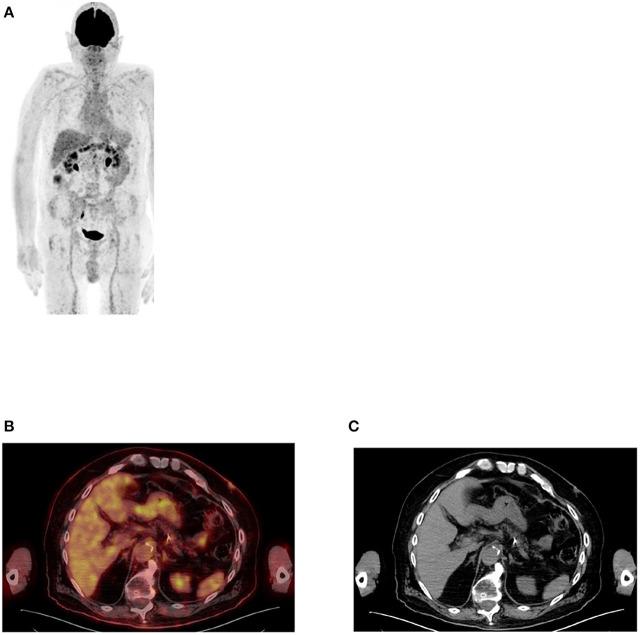

Since its introduction into clinical practice, multimodality imaging has revolutionized diagnostic imaging for both oncologic and non-oncologic pathologies. F-fluorodeoxyglucose (F-FDG) PET/CT imaging which takes advantage of increased anaerobic glycolysis that occurs in tumor cells (Warburg effect) has gained significant clinical relevance in the management of most, if not all oncologic conditions. Because FDG is taken by both normal and abnormal tissues, PET/CT imaging may demonstrate several normal variants and imaging pitfalls. These may ultimately impact disease detection and diagnostic accuracy. Imaging specialists (nuclear medicine physicians and radiologists) must demonstrate a thorough understanding of normal and physiologic variants in the distribution of F-FDG; including potential imaging pitfalls and technical artifacts to minimize misinterpretation of images. The normal physiologic course of F-FDG results in a variable degree of uptake in the stomach, liver, spleen, small and large bowel. Urinary excretion results in renal, ureteric, and urinary bladder uptake. Technical artifacts can occur due to motion, truncation as well as the effects of contrast agents and metallic hardware. Using pictorial illustrations, this paper aims to describe the variants of physiologic F-FDG uptake that may mimic pathology as well as potential benign conditions that may result in misinterpretation of PET/CT images in common oncologic conditions of the abdomen and pelvis.

自从多模态成像技术引入临床实践以来,它已经彻底改变了肿瘤和非肿瘤疾病的诊断成像。利用肿瘤细胞中发生的无氧糖酵解增加(瓦伯格效应)的F-氟脱氧葡萄糖(F-FDG)PET/CT成像,在大多数(即使不是全部)肿瘤疾病的管理中已具有重要的临床意义。由于正常组织和异常组织都会摄取FDG,PET/CT成像可能会显示出几种正常变异和成像陷阱。这些最终可能会影响疾病检测和诊断准确性。成像专家(核医学医师和放射科医生)必须充分了解F-FDG分布中的正常和生理变异;包括潜在的成像陷阱和技术伪影,以尽量减少对图像的错误解读。F-FDG的正常生理过程会导致胃、肝脏、脾脏、小肠和大肠出现不同程度的摄取。尿液排泄会导致肾脏、输尿管和膀胱摄取。由于运动、截断以及造影剂和金属硬件的影响,可能会出现技术伪影。本文旨在通过图片说明,描述可能模仿病变的生理性F-FDG摄取变异,以及在腹部和骨盆常见肿瘤疾病中可能导致PET/CT图像误判的潜在良性情况。